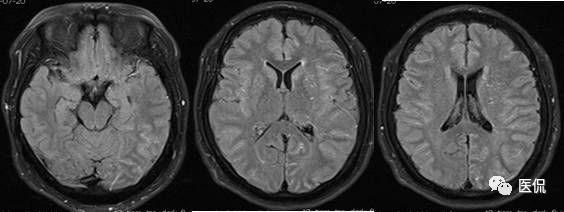

flair序列

flair序列上的白质改变,左侧为脑室周围白质改变,右侧为深部白质改变.